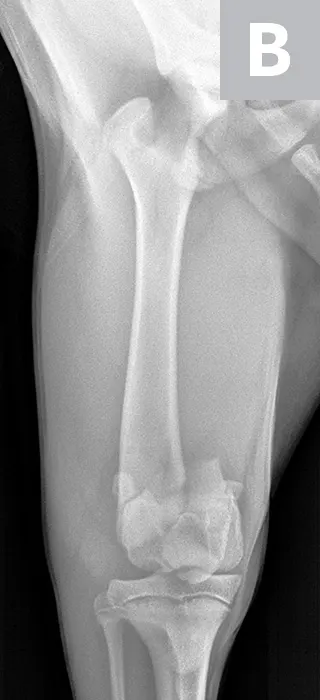

Hydromorphone (0.05 mg/kg IV) was administered for analgesia, and lateral and ventrodorsal thoracic radiographs were obtained to evaluate for thoracic trauma. Radiographic findings were within normal limits; however, lateral and craniocaudal radiographs of the right pelvic limb (Figure 1) revealed a Salter-Harris type II fracture of the distal femur with caudal and medial displacement.

Figure 1

Lateral (A) and craniocaudal (B) radiographs of this patient’s femur. A Salter-Harris type II fracture with caudal and medial displacement is present in the distal femur. The metaphyseal component (A; arrow) and the epiphyseal component (arrowhead) can be noted.